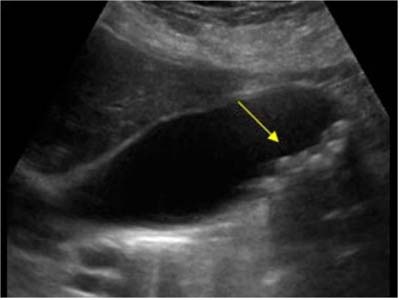

所謂“多發(fā)性膽結(jié)石”,一般是與“單發(fā)結(jié)石”區(qū)別而論的,就是指膽囊內(nèi)不僅是一枚膽囊結(jié)石,而是可以探及多個或十多個,甚至數(shù)十個結(jié)石影像,稱為“多發(fā)性膽結(jié)石”。B超影像中可發(fā)現(xiàn)多個強(qiáng)回聲光團(tuán),可移動,后伴聲影。

多發(fā)性膽結(jié)石超聲影像